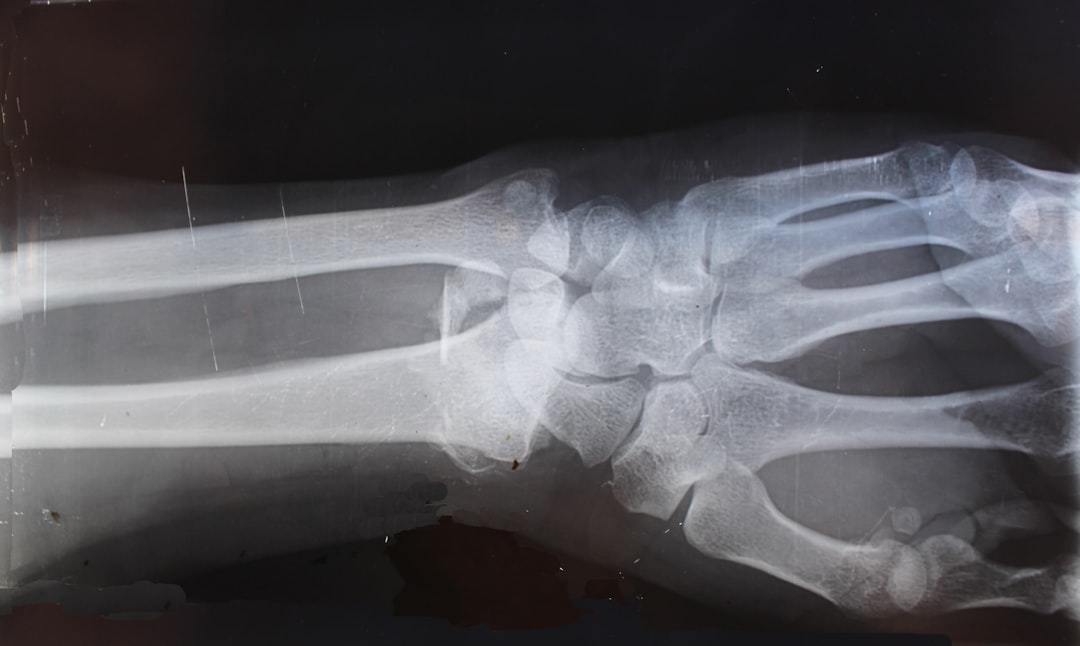

손가락 관절염은 손가락 관절에 발생하는 염증으로, 손가락 관절염 증상은 통증, 부기 및 관절의 경직 등을 포함합니다. 이 병은 주로 나이가 많아질수록 발생하지만, 젊은 세대에서도 견딜 수 없는 통증으로 고통받는 이들이 있습니다. 관절의 연골이 마모되거나 면역 체계가 잘못 작동하면서 염증이 생기는 상황들이 관절염을 야기할 수 있습니다. 만일 손가락 관절염의 초기 증상에 주의를 기울이지 않는다면, 더 심각한 문제로 번질 수 있습니다. 그러니 이 주요 증상을 인지해 두는 것이 중요합니다.

단순한 염증이 아닌 손가락 관절염은 라이프스타일에 맞춰 다양한 관리가 필요합니다. 일상적인 활동에서 나타날 수 있는 통증은 단순히 불편함을 넘어, 삶의 질을 크게 저하시킵니다. 이를 위해 정기적으로 병원을 방문하고 손가락 관절염 병원을 통해 전문적인 진단과 치료를 받는 것이 매우 중요합니다. 여러 가지 관리 방법이 존재하지만, 개인의 상태에 맞는 방법을 찾아가는 과정이 필요합니다. 이제 각 치료 방법에 대해 깊이 있게 알아보겠습니다.